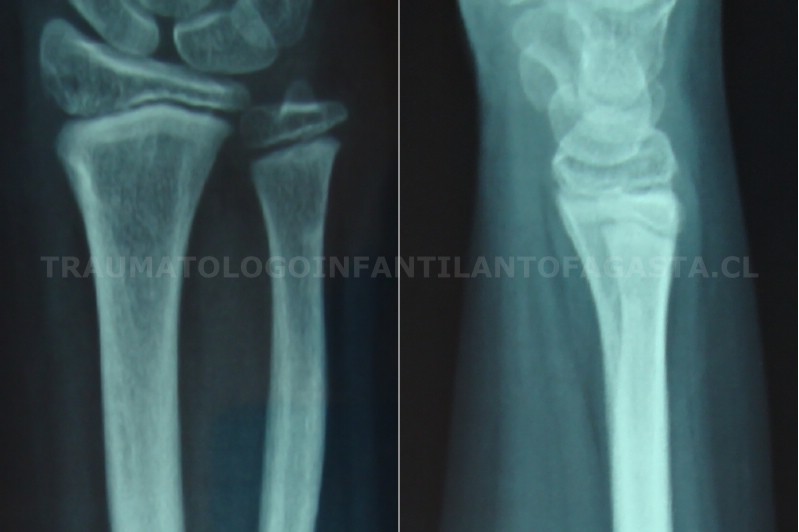

Fractura de muñeca